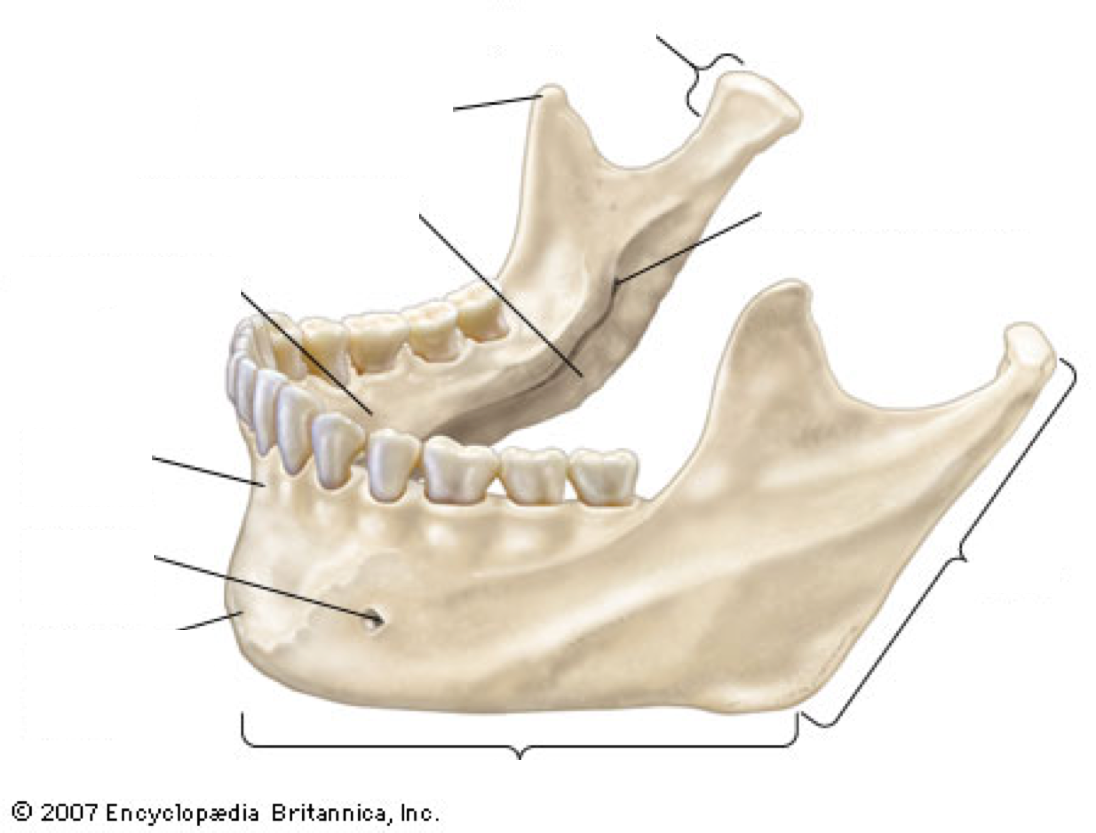

Label image

Label the mandible